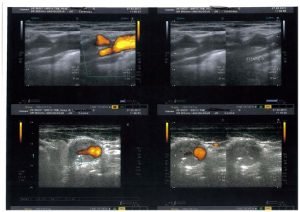

Exemple d’angioplastie carotidienne pour resténose à 6 mois après chirurgie.

Les resténoses précoces après endartériectomie carotidienne sont rares.

Le doppler échographie fait à 6 mois et un an après l’opération permet de les détecter.

La resténose précoce est fibreuse. C’est une bonne indication d’angioplastie carotidienne endoluminale avec stent.

L’indication à ce traitement a été décidé en staff multidisciplinaire sur avis du chirurgien et avec information et accord du malade.

Cette intervention a été réalisée sous double traitement anti aggrégant plaquettaire.